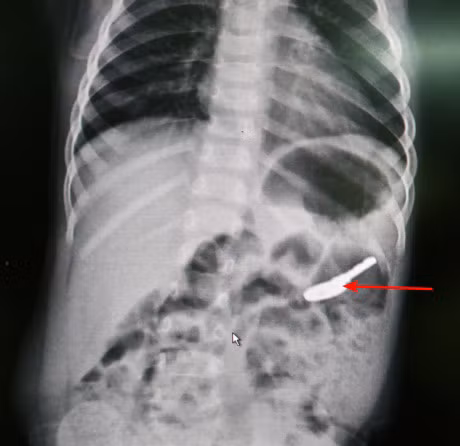

Sau khi tiến hành các thủ thuật và dựa trên hình ảnh chụp X.Quang, bác sĩ phát hiện trong dạ dày của bé T có 1 vật thể là chiếc chìa khóa có kích thước khoảng 3,5cm. Khi gắp bỏ dị vật sức khỏe bệnh nhân đã ổn định, ăn uống tốt và được xuất viện.

Thời gian gần đây nhiều trẻ nhỏ ở Quảng Ninh nuốt phải dị vật sắc nhọn. Ảnh: V.Nhị